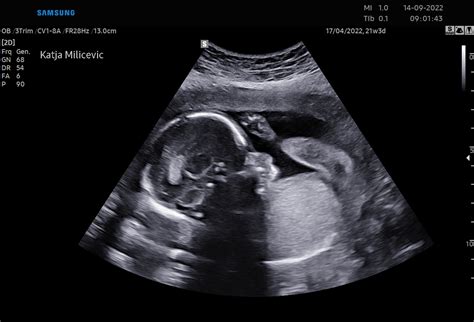

- 19. in 20. teden: Možgani se intenzivno razvijajo, rast ploda se nadaljuje. Nosečnice, še posebej tiste, ki prvič pričakujejo otroka, bodo morda že lahko prvič občutile nežne gibe. V tem času se običajno opravi morfološki ultrazvočni pregled ploda, ki podrobno oceni njegov razvoj in lego posteljice. V 20. tednu plod meri približno 25 cm v dolžino in tehta okoli 300 g. Na koži se pojavi verniks, bela mastna zaščitna snov.

- Morfologija ploda (20. teden): Obširnejši ultrazvočni pregled, ki oceni rast in razvoj ploda, preveri posteljico ter omogoči vpogled v premike in srčni utrip. Pogosto se na tem pregledu izve tudi spol otroka.